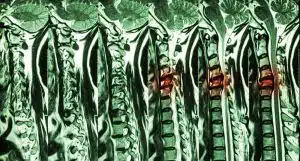

Spinal cord compression is a serious injury that can often result from a car accident. The spinal cord is a bundle of nerves that runs down the back, and it plays a vital role in transmitting information between the brain and the rest of the body. Compression of the spinal cord can occur when there is pressure on the nerves, which can lead to a range of symptoms and complications.

In car accidents, spinal cord compression is often caused by a sudden, forceful impact that jolts the spine and causes it to bend or twist unnaturally. This can lead to a range of injuries, including fractures of the vertebrae (the bones that make up the spine) and herniated discs (when the cushioning discs between the vertebrae rupture or bulge out of place). These injuries can put pressure on the spinal cord and cause compression.

If you have been injured in a car accident near or in Boston and are experiencing any of these symptoms, it is important to seek medical attention immediately. A doctor can perform a physical examination and imaging tests (such as an MRI or CT scan) to diagnose spinal cord compression and determine the best course of treatment.